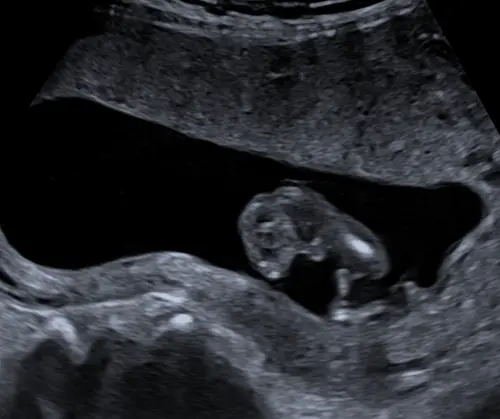

🩵🩷? 13+5

Wie wil een gokje wagen? Dit is baby 2. Volgende bericht deel ik baby 1 van de tweeling. Ben zoo benieuwd!